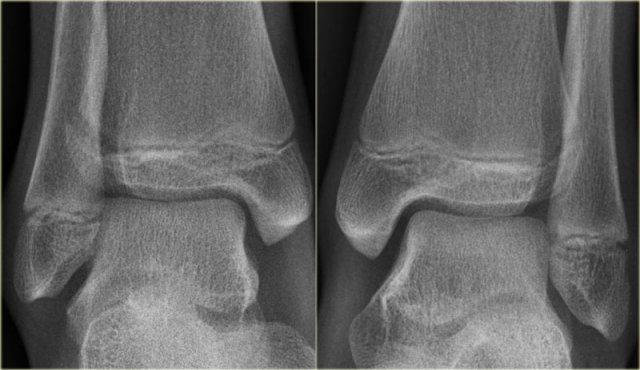

Đây là hình ảnh của một ca bệnh cực kỳ khó.

Bệnh nhân nữ bị bong gân cổ chân và đau cả hai bên trong và ngoài.

Bệnh nhân được bác sĩ đa khoa chuyển đến khoa Chẩn đoán Hình ảnh.

Kỹ thuật viên chụp các tư thế chuẩn gồm thẳng (AP), Mortise và nghiêng, sau đó trình bày cho bác sĩ X-quang, người đã khá băn khoăn khi đọc phim.

Hãy đọc hình ảnh trước, sau đó tiếp tục đọc phần giải thích.

Các dấu hiệu bao gồm:

Phù nề phần mềm cả hai bên trong và ngoài (mũi tên đỏ).

Đặc biệt, phù nề phía trong nên gợi ý khả năng chấn thương xoay ngoài – sấp (Weber C). - Đường thấu quang trên tư thế Mortise (mũi tên đen) và tư thế nghiêng. Dấu hiệu này nên gợi ý gãy tertius.

Bác sĩ X-quang quyết định chỉ định CT trước để xác định xem có thực sự có gãy tertius hay không.

Tiếp tục xem hình ảnh CT và bạn sẽ ngạc nhiên.

Hãy cuộn qua các lát cắt.

Thật đáng ngạc nhiên khi một mảnh tertius lớn như vậy lại rất khó nhìn thấy trên phim X-quang.

Cũng lưu ý phù nề phần mềm phía trong gợi ý đứt dây chằng bên trong (mũi tên).

Bạn có thể đoán được đây là loại chấn thương gì không?

Phù nề phần mềm phía trong và gãy tertius đều là dấu hiệu của chấn thương Weber C hoặc chấn thương xoay ngoài – sấp.

Do không thấy gãy xương mác trên phim X-quang cổ chân, phải có gãy xương mác cao.

Khi khám lâm sàng, có phù nề nhẹ phía trong và mặc dù bệnh nhân không than đau ở vùng cao hơn của cẳng chân, vẫn có điểm đau khi ấn vào xương mác.

Vị trí này được đánh dấu và phát hiện đường gãy.

Ca bệnh này minh họa tầm quan trọng của phù nề phần mềm phía trong cũng như dấu hiệu gãy tertius.

Theo phân loại Lauge Hansen, chúng ta có thể kết luận rằng bệnh nhân này đầu tiên bị đứt dây chằng bên trong (giai đoạn 1), tiếp theo là đứt dây chằng chày mác trước (giai đoạn 2), gãy xương mác cao (giai đoạn 3) và cuối cùng là bong mắt cá sau, tức là chấn thương xoay ngoài – sấp (PE) giai đoạn 4.

Trong phẫu thuật, cổ chân được xác định là không vững và vít cố định khớp chày mác đã được đặt vào.

Có chỉ định cố định gãy mắt cá sau vì mảnh gãy chiếm hơn 25% diện khớp của đầu dưới xương chày.